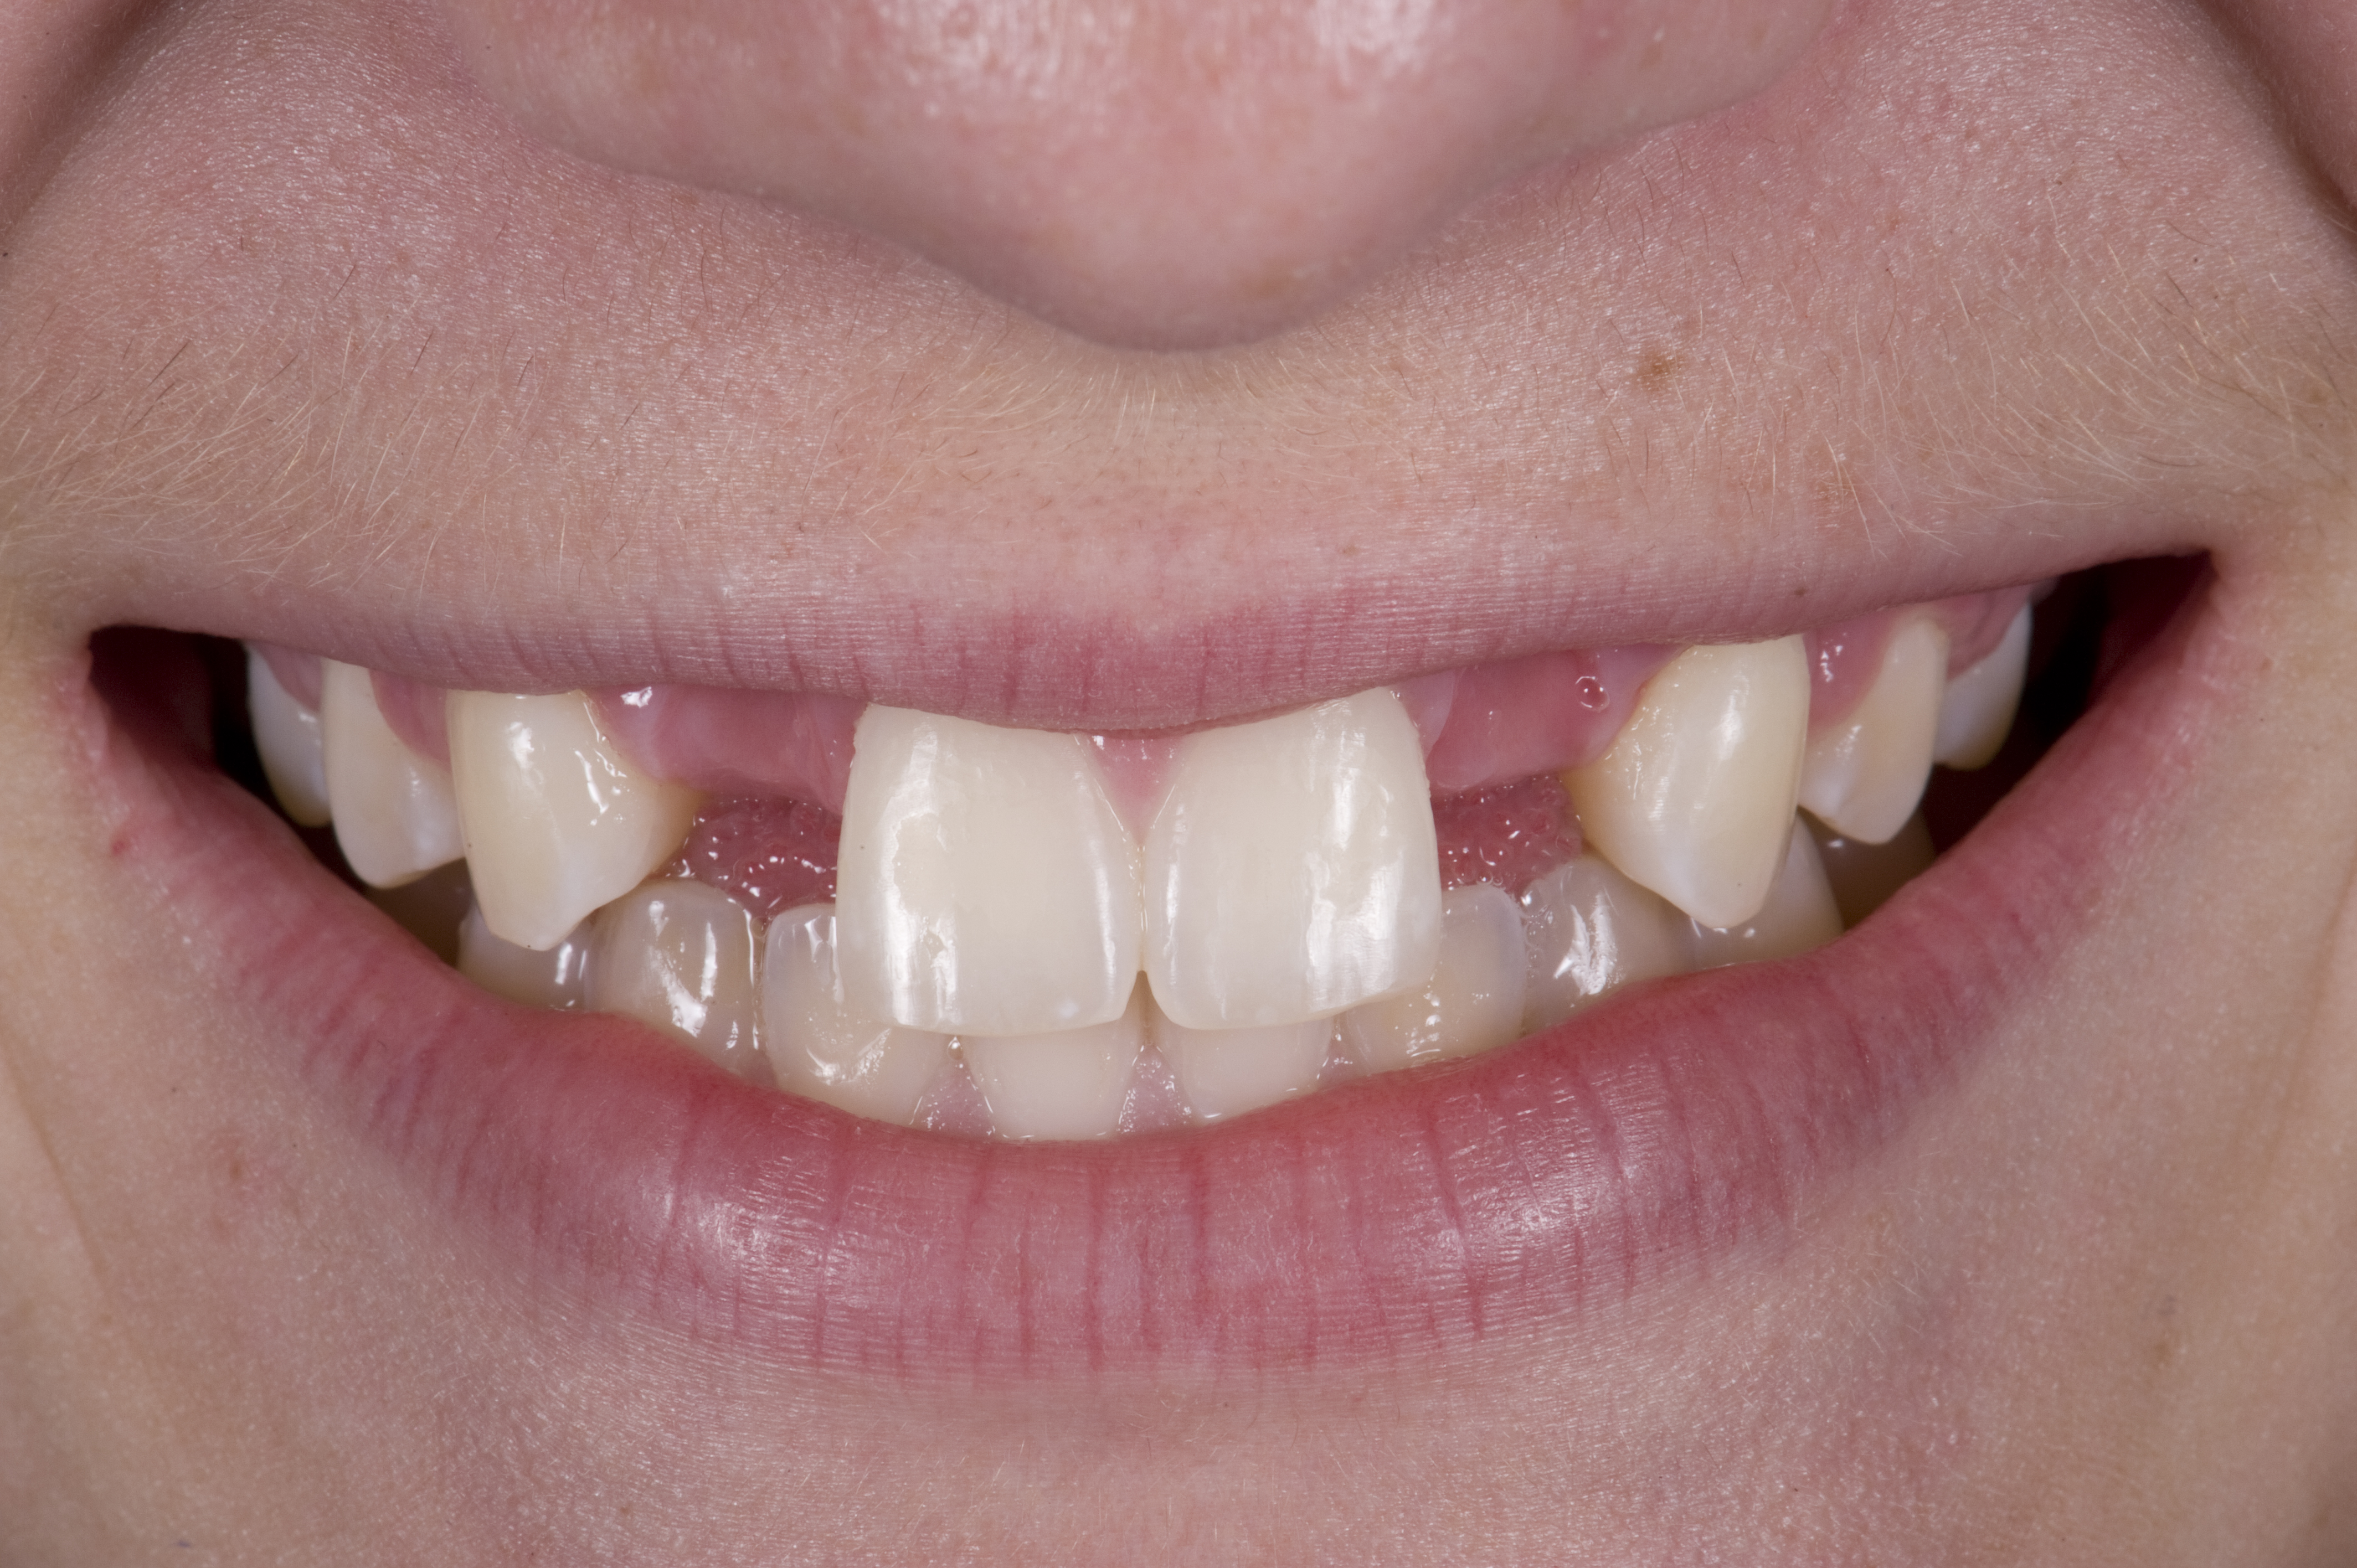

(1.) Initial presentation. Note midline shift to right, missing right lateral incisor, and diminutive left lateral incisor in crossbite.

Figure 1

A 14-year-old patient presented to the office with his mother (Figure 1). His chief complaint involved the large spaces between the teeth created by his missing right maxillary lateral incisor and his small left maxillary lateral incisor. He desired to replace the missing tooth with an implant and create a beautiful smile. Upon examination, he was found to have a class I canine and molar relationship, but because he had a tooth size/arch size discrepancy and space distal to the right central incisor, the remaining incisors had drifted to the right. The left maxillary lateral incisor was peg-shaped and in a cross bite position. Studies have shown a clear association between congenitally missing teeth and reduced tooth size.59-62 Because he was only 14 years old at the time and could not have implants placed until the cessation of growth (somewhere in the vicinity of 22 years old), he was sent to the orthodontist for alignment of the teeth.16,17 After 2 years of orthodontics, the appliances were removed, and his tooth coloration was improved using carbamide peroxide bleaching (Figure 2). Because some form of provisional needed to be placed until he was finished growing, a double-wing metal resin-bonded bridge was chosen. As discussed earlier, this is the ideal transitional prosthesis for patients that have congenitally missing maxillary lateral incisors. The benefits of this type of prosthesis include its ability to be removed and rebonded during the surgical phase of treatment and its ability to retain the roots in their proper position after orthodontic treatment.16 The final plan for the patient was to increase the width of the central and the maxillary left lateral incisor, utilizing porcelain laminate veneers to achieve the appropriate width/length ratio of 80%. A wax-up was created to idealize tooth size, a putty matrix was made from the wax-up to facilitate bonding of the incisors, and a non-precious, double-wing metal resin-bonded bridge was fabricated for lateral incisor replacement. Once the teeth were bonded to ideal size, the “Maryland Bridge” was fabricated from a polyvinyl arch impression with the newly bonded teeth (Figure 3). The metal frame was cast from a non-precious alloy to allow for fabrication of a very thin frame and to create a better surface for bonding. After sandblasting the internal aspect of the frame with CoJet™ silica (3M ESPE), accomplishing salinization, and executing cementation with a dual-cure resin cement, a fairly good adhesion to the frame was anticipated.29 The enamel surface was etched with phosphoric acid for 30 seconds, the primer (Single Bond Plus, 3M ESPE) was applied to both the internal surface of the sandblasted framework and the etched enamel, and the bridge was cemented with RelyX™ ARC (3M Espe) dual-cured resin cement (Figure 4 and Figure 5).